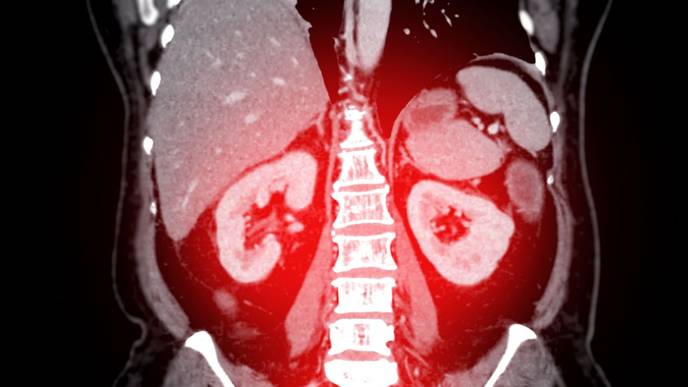

Urolithiasis Directly Linked to Osteoporosis, Finds Study

Researchers have found that urolithiasis, commonly known as kidney stones, has a direct causal relationship with osteoporosis (OP), independent of environmental factors. A recent study was published in The Journal of Clinical Endocrinology and Metabolism by Zijie Z. and colleagues. This study utilized Mendelian randomization (MR) and other genetic analyses to uncover the biological mechanisms linking these two conditions, emphasizing the importance of regular OP screening for patients with urolithiasis.